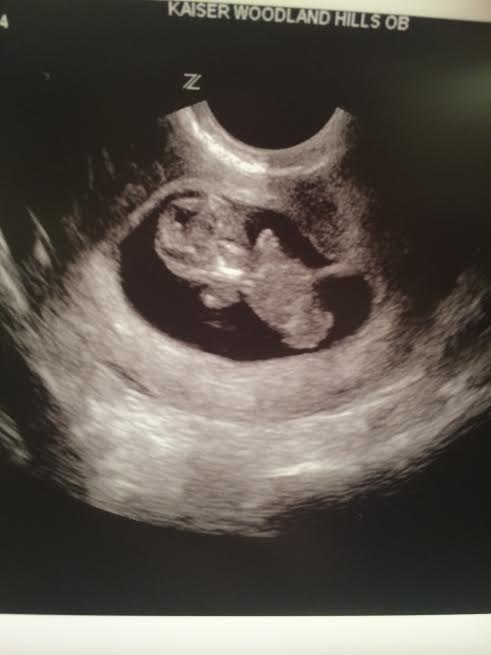

how far along: 22 weeks, 2 days

gender: a little miss!!